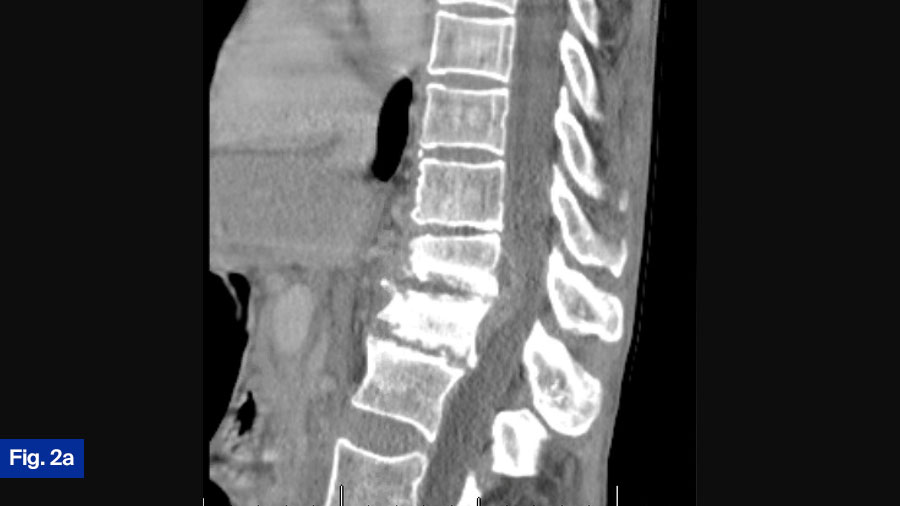

- CT scan: Demonstrated bony destruction and increased segmental kyphosis at T11-T12 (Figure 2a).

- MRI scan: Demonstrated a large ventral epidural phlegmon with moderate cord compression and thoracic hyperintensity with end-plate destruction (Figure 2b).

- Upright radiographs: Further evaluated spinal stability (Figure 2c).